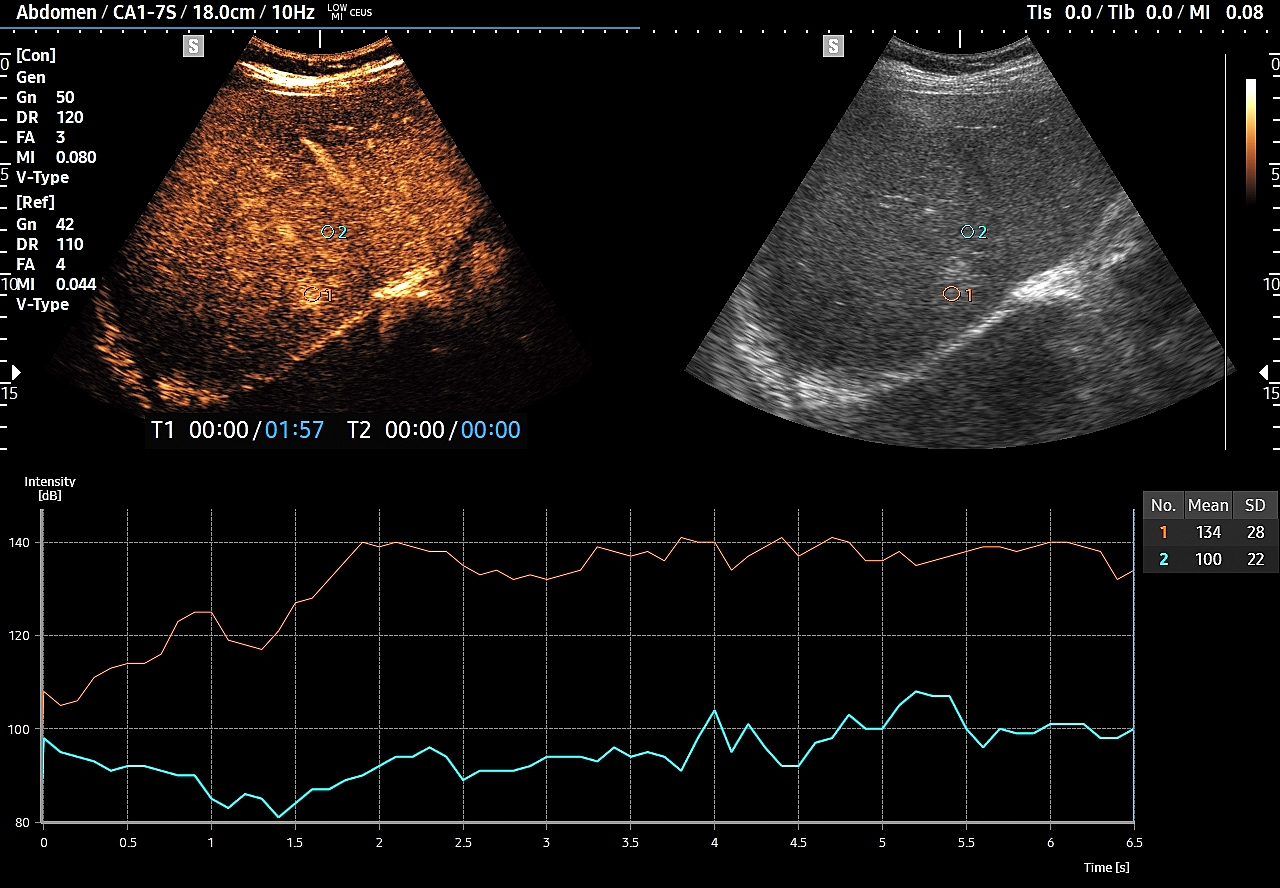

W razie braku pewności co do wypełnienia guzka w stosunku do natywnego miąższu wątroby, tj. słabo dostrzegalnych wizualnie różnic, pomocne może być wykorzystanie w ramach obróbki postprocessing’owej ilościowej oceny wypełnienia kontrastem poszczególnych obszarów, tj. guzka i prawidłowego miąższu, w ramach analizy TIC (ang. time intensity curve). Metoda ta polega na umieszczeniu jednego znacznika w zmianie ogniskowej, drugiego w kolejnym obszarze, a następnie porównania ich obu pod kątem intensywności sygnału na osi czasu.